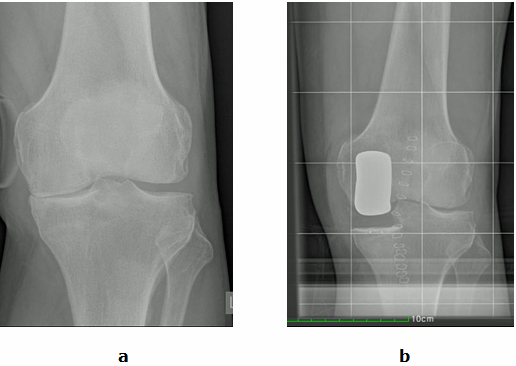

Abb.1: a Der Innere Gelenkspalt (Pfeil) ist aufgehoben. Der Äußere Gelenkspalt ist intakt.

b Der Innere Gelenkspalt wurde durch eine Schlittenprotheseersetzt (Gelenkteilersatz).